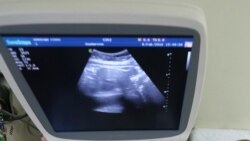

Türkmenistanda ýaňy-ýakynda güýje giren gadaganlyga garamazdan, abort etdirýänleriň sany azalmady we indi köp sanly aýal islenilmeýän göwreliligi aradan aýyrmak üçin para bermeli bolýarlar diýip, aýallar we lukmanlar aýdýarlar.